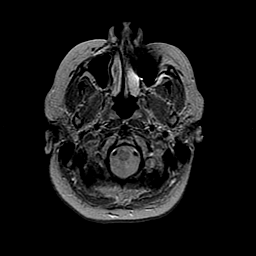

MR Study #2 -- Slice #7